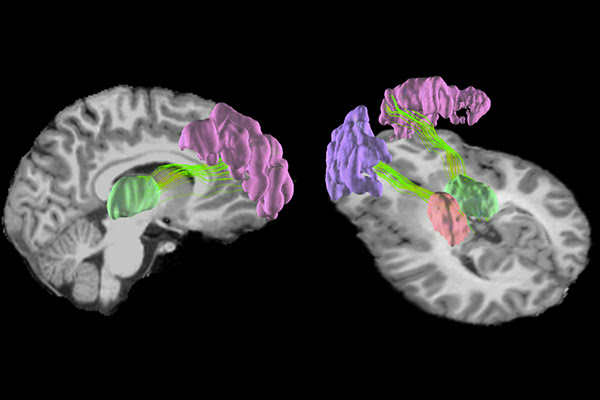

Magnetic resonance imaging (MRI) brain scans have revealed that playing a single season of high school football can cause microscopic changes the grey matter in young players’ brains. These changes are located in the front and rear of the brain, where impacts are most likely to occur, as well as deep inside the brain. Image by Nan-Jie Gong and Chunlei Liu, UC Berkeley.

They found significant changes in the structure of the grey matter in the front and rear of the brain, where impacts are most likely to occur, as well as changes to structures deep inside the brain.

The changes were concentrated in the front and rear of the cerebral cortex, which is responsible for higher-order functions like memory, attention and cognition, and in the centrally located thalamus and putamen, which relay sensory information and coordinate movement.